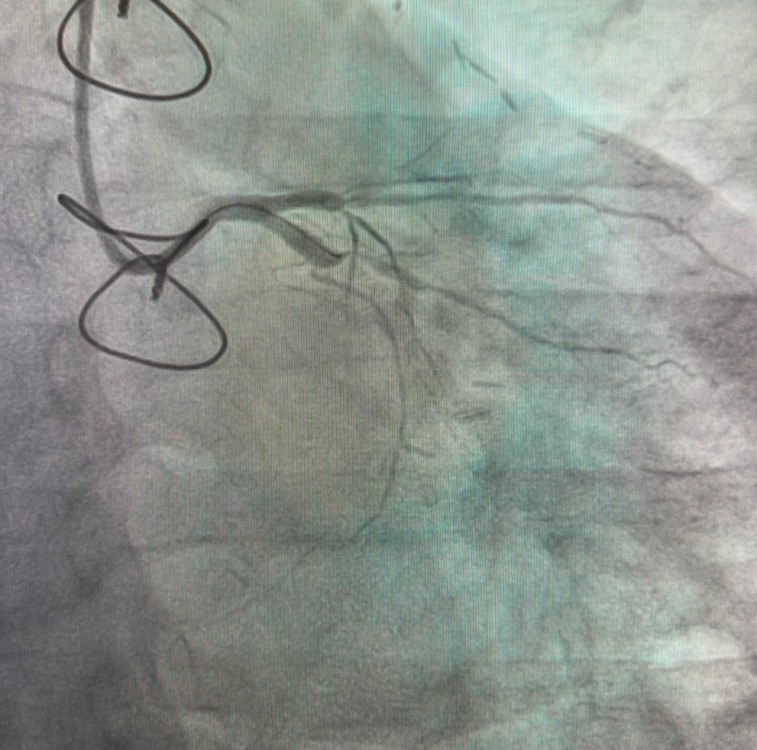

После госпитализации и обследования кардиологи диагностировали сложное атеросклеротическое поражение огибающей артерии с полным ее закрытием.

Для восстановления кровотока врачами была выполнена коронарография с последующей установкой стентов с помощью малоинвазивных рентгеноэндоваскулярных технологий.

Специалисты отметили, что благодаря оперативному вмешательству пациент смог избавиться от болей и вернуться к активной жизни. Сейчас мужчина даже путешествует.